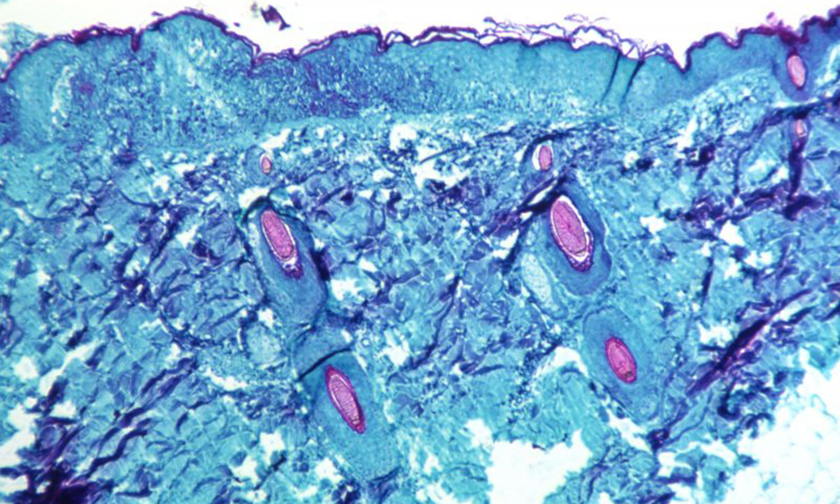

На первой стадии у больного наблюдается подъем температуры, боли в мышцах, боли в суставах, головная боль, распухшие лимфоузлы. Вскоре появляется сыпь, она превращается в папулы, наполненные жидкостью, которые через некоторое время лопаются, образовывая на этом месте корочку.

Фото: CDC / AP